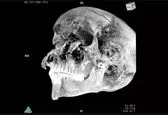

ایسنا: محققان میگویند شواهد جدید نشان میدهد فرعون مصری که با نام تائو دوم شناخته میشود در میدان نبرد کشته شده است.